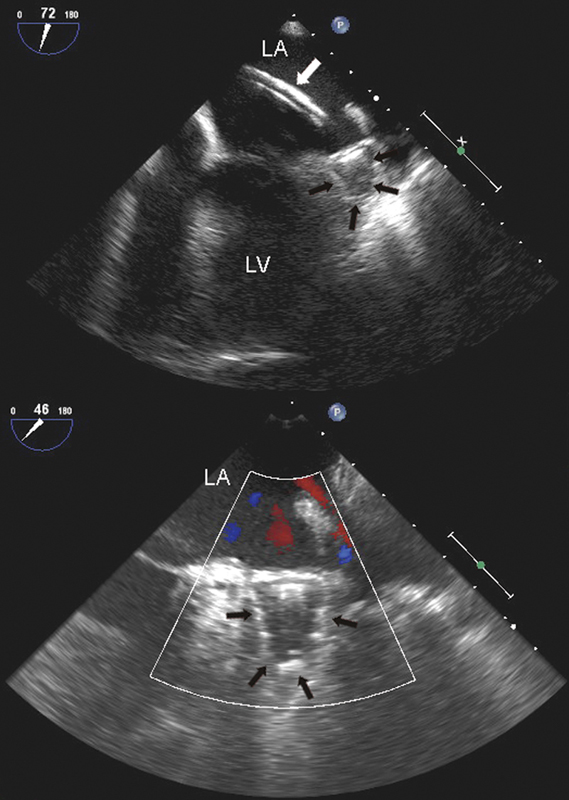

فحوصات تشخيصية لبعض امراض القلب والشرايين التاجية